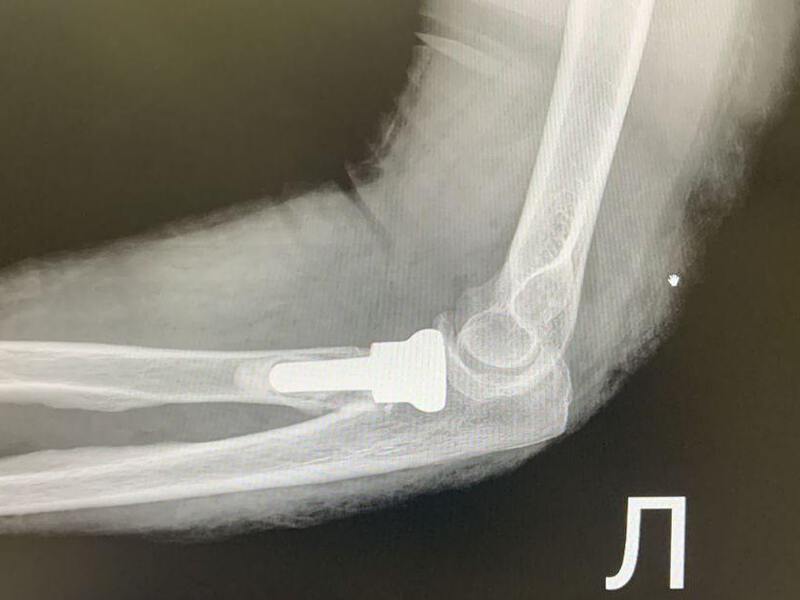

Первой пациентке 66 лет — у неё диагностировали оскольчатый перелом головки лучевой кости. Второй случай сложнее: 55-летняя женщина получила множественные травмы — перелом метаэпифиза левой лучевой кости, перелом локтевой кости в верхней трети и оскольчатый перелом головки лучевой кости.

Но при оскольчатых переломах головки лучевой кости, когда она дробится на множество фрагментов, ситуация иная. Собрать мелкие осколки и надёжно зафиксировать их пластиной практически невозможно. Требуется другой подход.

Решение: эндопротез

Врачи выбрали протезирование головки лучевой кости. Суть операции в следующем:

- удаляют повреждённые костные фрагменты;

- формируют костномозговой канал в проксимальном отделе лучевой кости;

- устанавливают эндопротез из биосовместимого материала.

Как пояснил заведующий травматологическим отделением, такое вмешательство требует не только высокой квалификации, но и специального опыта. В Наро-Фоминской больнице обе операции прошли успешно.